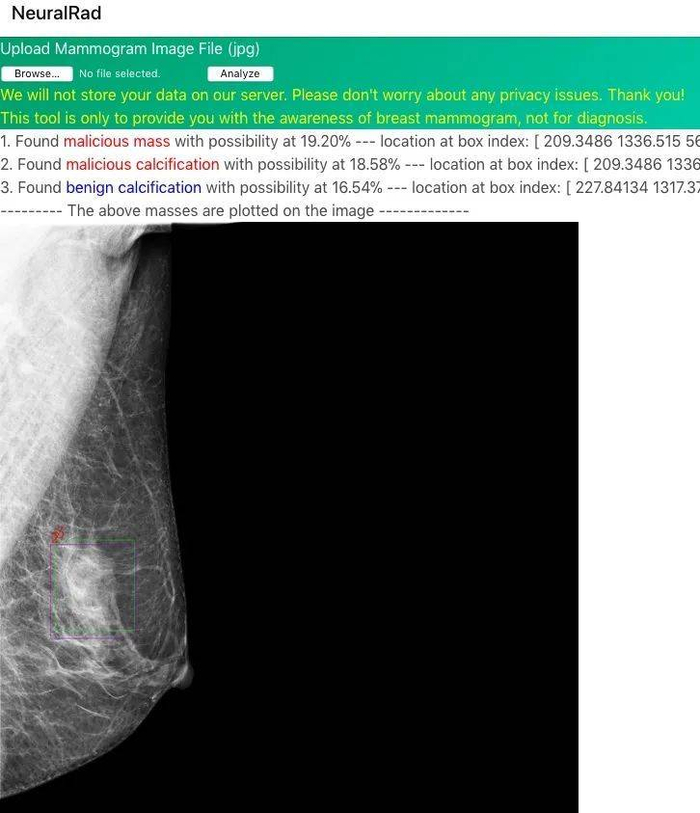

2018 年,一位名叫 coolwulf 的楼主开了个帖子,说自己做了一个网站。

用户只要上传自己的 X 光影像图片,就能让 AI 为自己快速诊断乳腺癌病情,肿瘤识别的准确率,也已经达到 90%。

简单来说,就是让人工智能帮你“看片子”,准确率还几近媲美专业医生,并且完全免费。

这个免费的 AI 检测乳腺癌网站,coolwulf 前后大概花了三个月的业余时间,忙得时候直接睡在办公室,最后终于在 2018 年上线。

他和差评君说,由于后台不保存数据,所以并不清楚具体有多少人使用过。

但在那段时间,他收到了很多患者的感谢邮件,不少都来自国人。

而且,用户真的用网站检查出了肿瘤,尤其对于医疗资源紧张地区的人们,相当于从死神手里抢下时间。